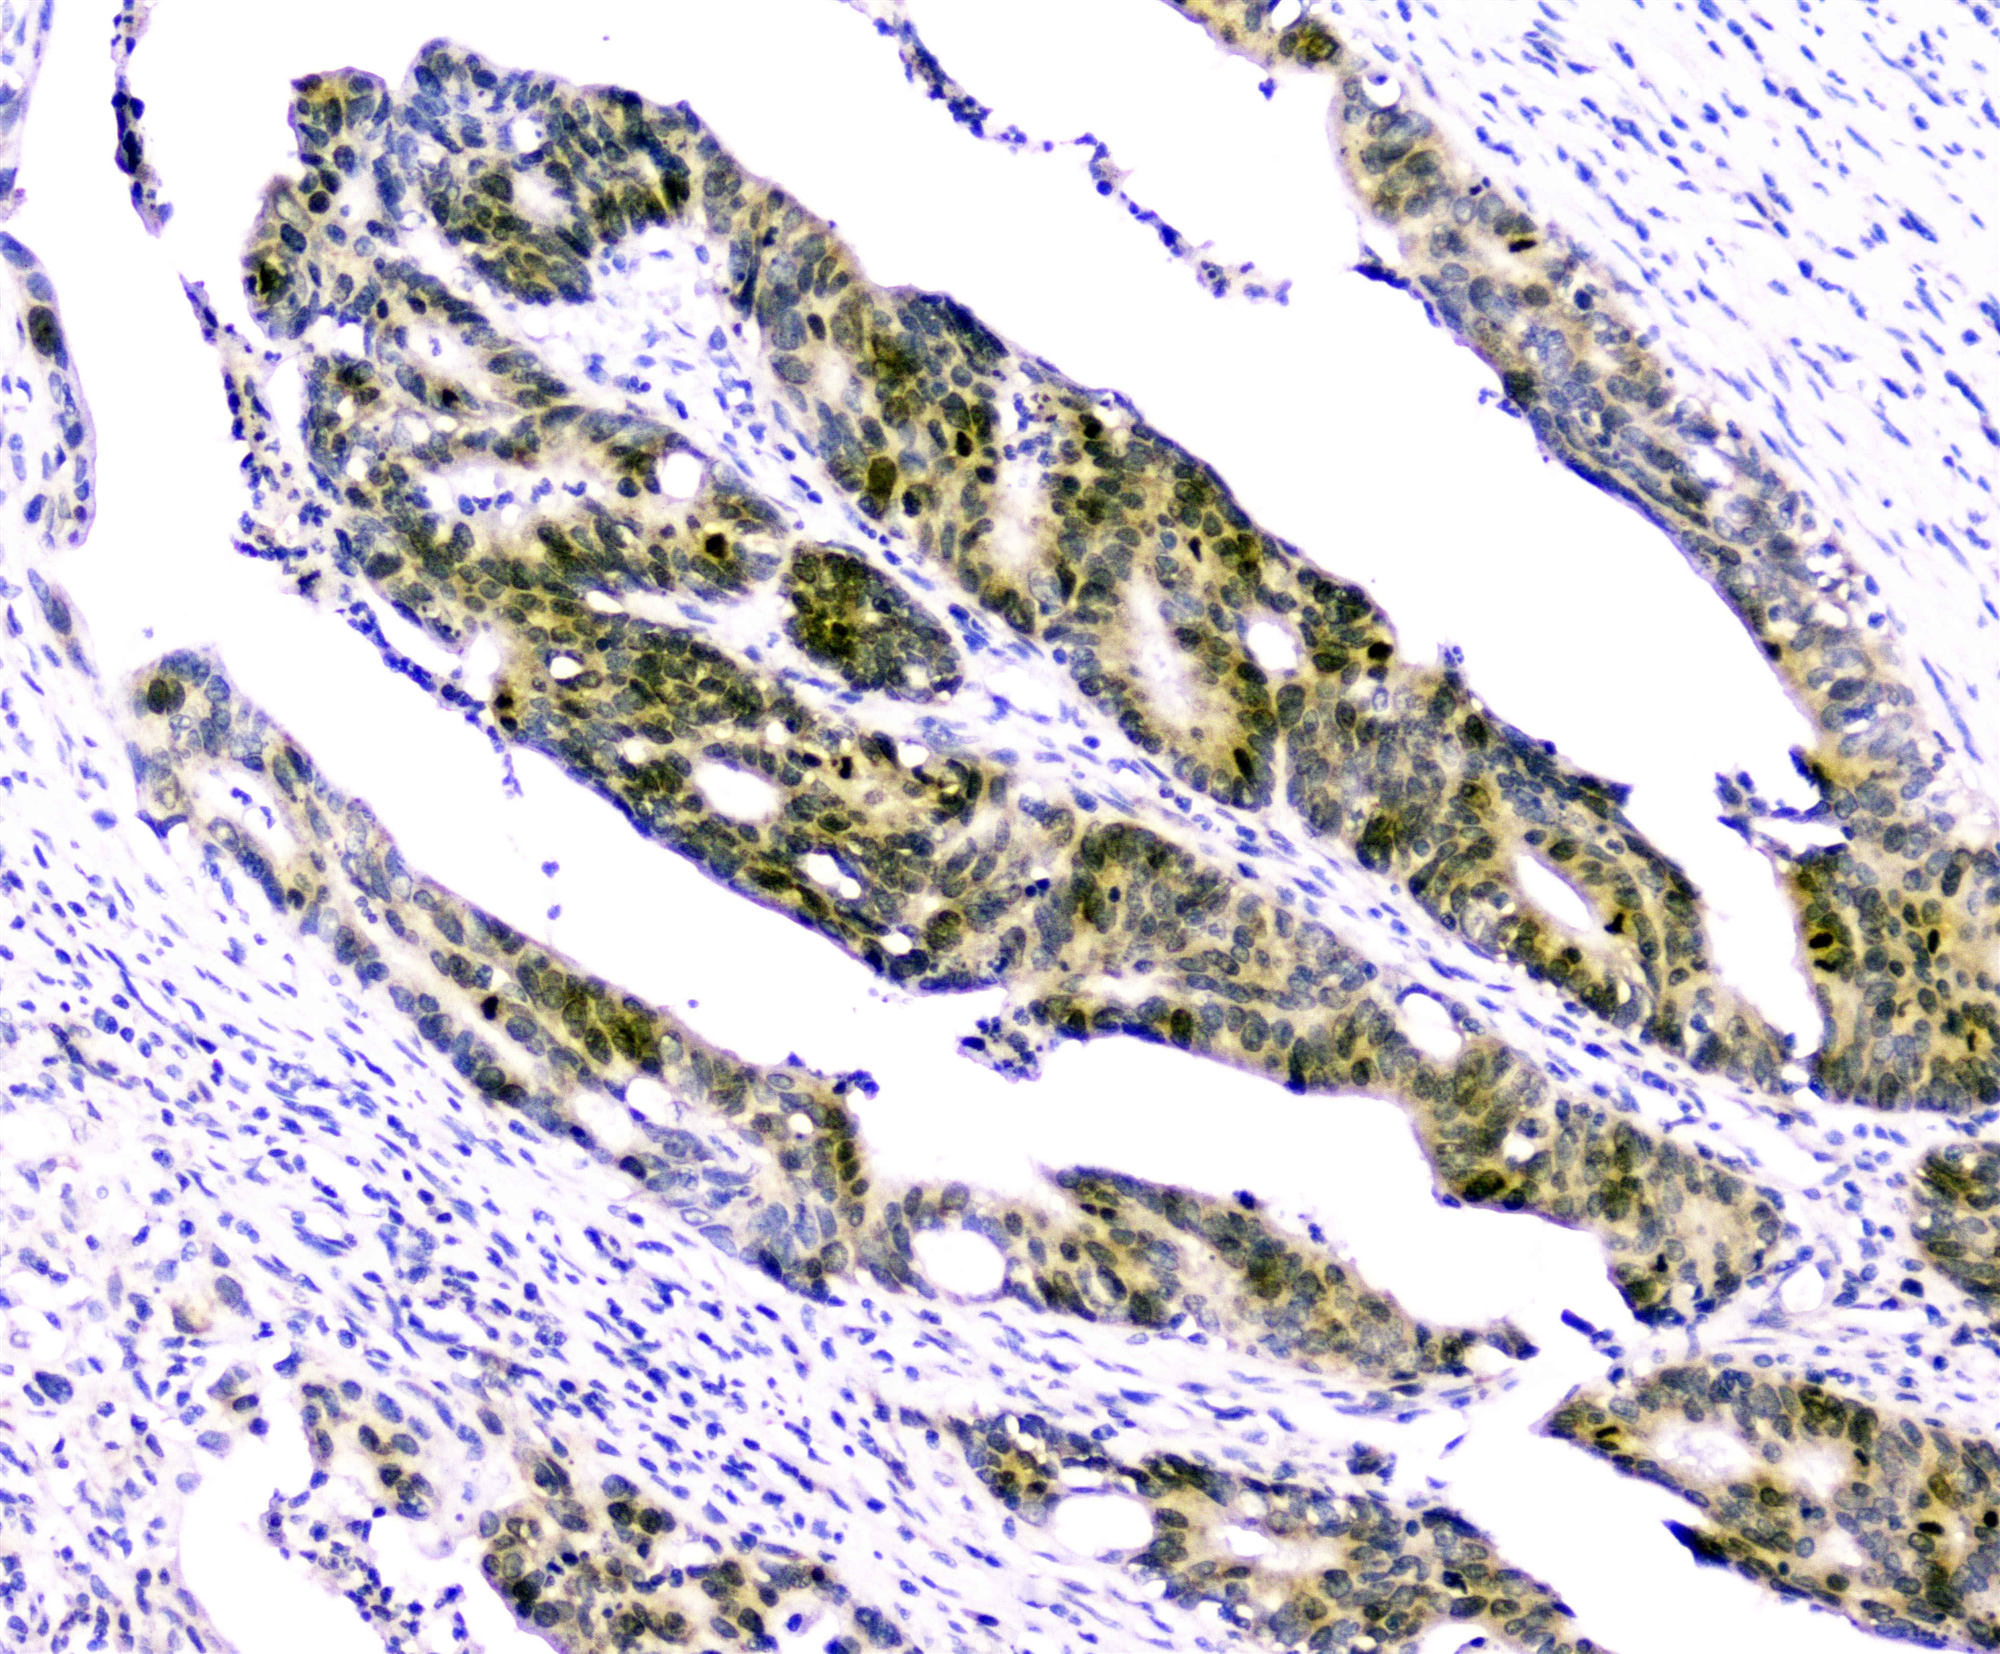

Figure 3. IHC analysis of Survivin using anti-Survivin antibody (A00379).

Survivin was detected in paraffin-embedded section of human intestinal cancer tissues. anti-Survivin Antibody (A00379) overnight at 4°C. Biotinylated goat anti-rabbit IgG was used as secondary antibody The tissue section was developed using Strepavidin-Biotin-Complex (SABC)(Catalog # SA1022) with DAB as the chromogen.